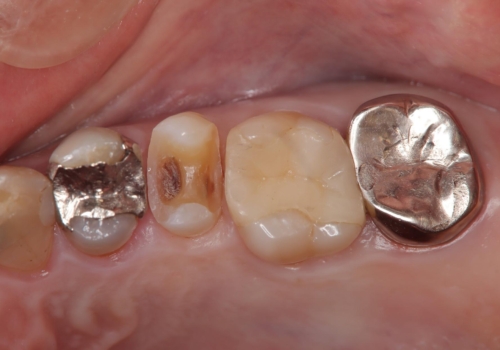

- 金属の詰め物が外れた状態で長期間過ごされた患者様が、歯を治したいとのことで来院されました。良好な長期予後が期待でき、歯質をできるだけ残せるセラミック治療を即日で行いました。

治療途中で虫歯も綺麗に除去しています。術後経過良好で、患者様も満足されています。他にも治療が必要な虫歯がありますので、順を追って治療する予定です。